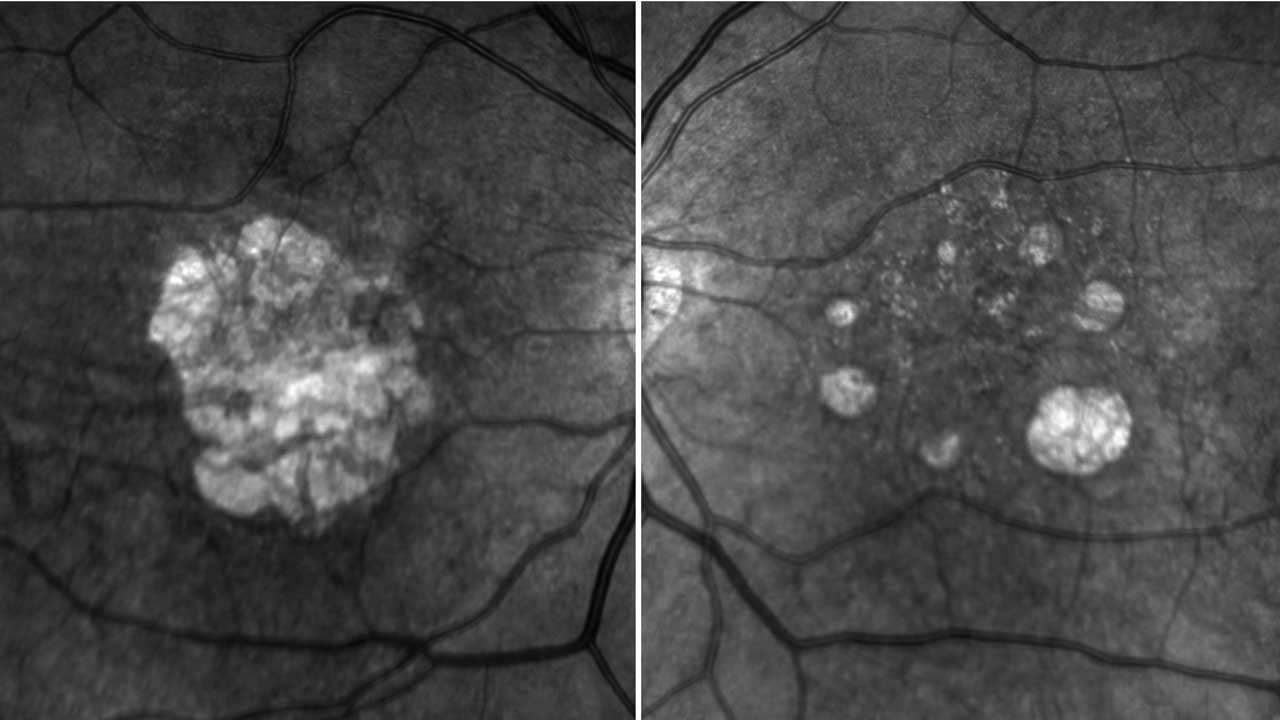

RG6501 (OpRegen, Lineage Cell Therapeutics) is a suspension of human retinal pigment epithelium cells delivered subretinally. A Phase 1 study showed improvement of the retinal structure on imaging and a Phase 2 trial will evaluate 60 patients.9